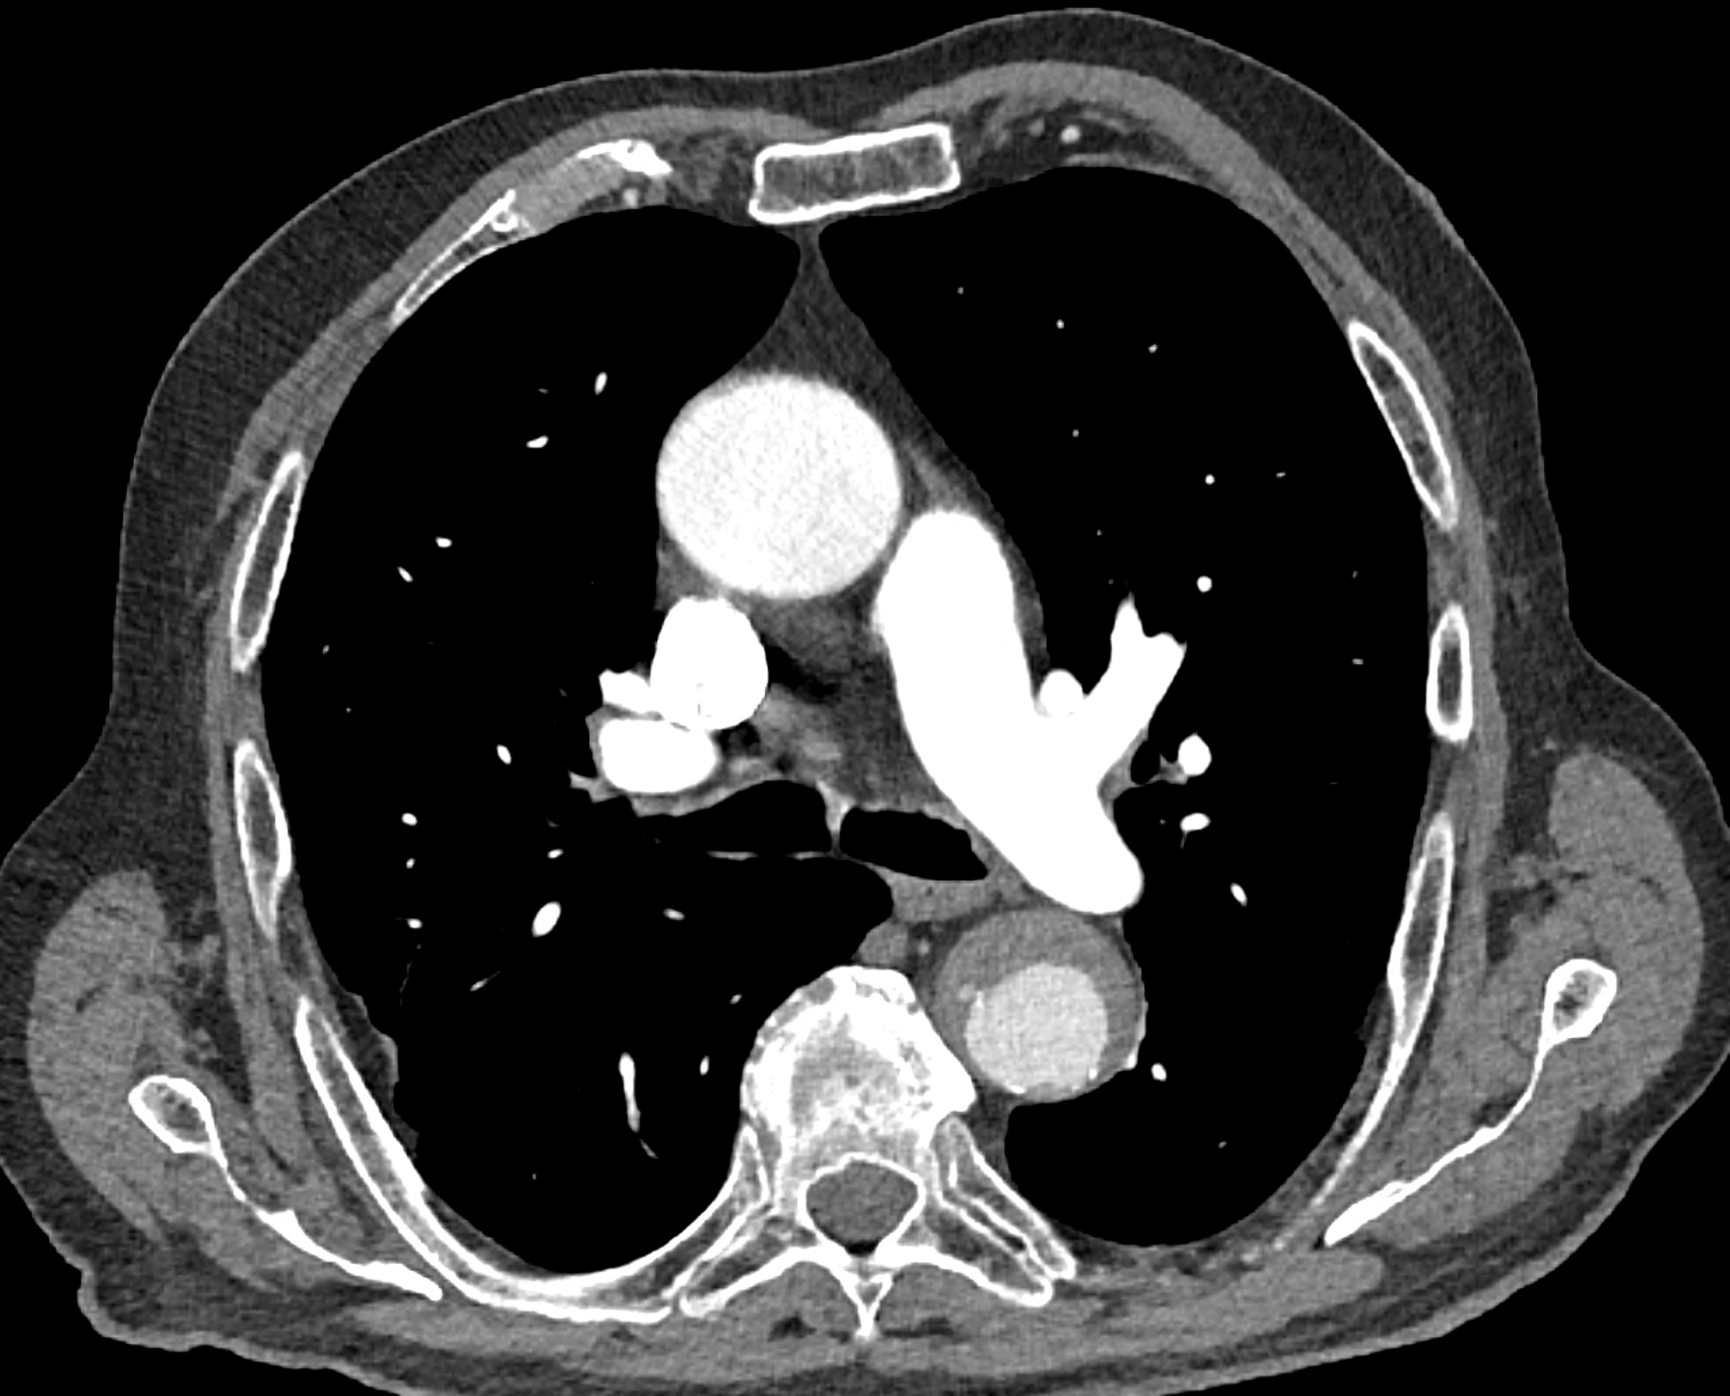

in patient chest pain, negative ECG but with elevated D-dimers was performed CTA of the chest to exclude highly suspected pulmonary embolism. No pulmonary embolism was see, but the pathology of the aortic arch and descending thoracic atorta. The images were consistent with aortic intramural hematoma type B according to the Stanford classification with incipient transformation in dissection – behind the subclavian artery, it is clear that the contrast agent is flowing into the intramural hematoma. Differentiation from wall thrombosis is facilitated by the presence of calcification in the detached intima, which is most clearly visible on virtual non-contrast imaging. The intramural hematoma itself exhibits different properties in terms of X-ray absorption. Coagulated blood is visible at the apex of the aortic arch, where it closely adjoins the area that is perfused and filled with contrast medium. There are other smaller areas filled with contrast medium at the sites of the intercostal arteries. These areas are secondary sites where the original intramural hematoma is channeled during its transformation into a classic aortic dissection.

Virtual non-contrast images help to distinguish between the intima and thus in the differential diagnosis of intramural hematoma versus wall thrombosis. Signs of fresh coagulated blood in IMH indicate bleeding into the aortic wall from the vasa vasorum. In contrast, monoenergetic images with lower energies of 40-55 keV highlight areas of intramural hematoma with active blood flow.

comparison of the the images 60, keV monoenergetic, virtual non-contrast (VNC), and iodine map images. The repercussion starts in the proximal tear of the intimate (the first three images), calcification in the intimate (next three images), tera at the level of the arising intercostal artery (last three images)